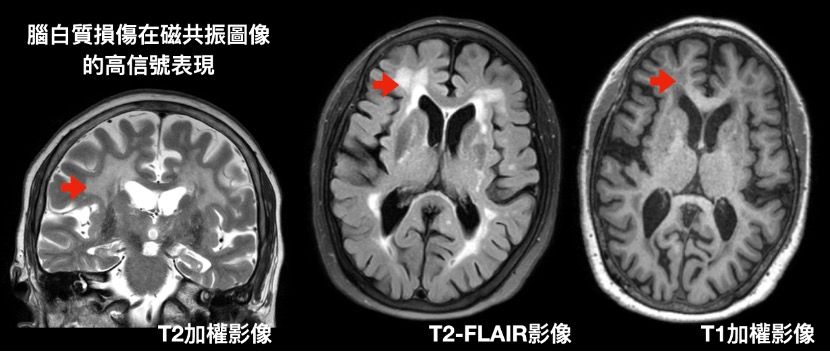

鍾芷萍表示,腦白質病變是腦部小血管疾病最常見的表徵,而腦部小血管疾病佔高齡族群30%的中風原因與45%的失智原因。腦白質病變的發生率、嚴重度,與人的年齡成正比,但臨床上仍缺乏一套獨立於實際年齡的客觀評估標準。